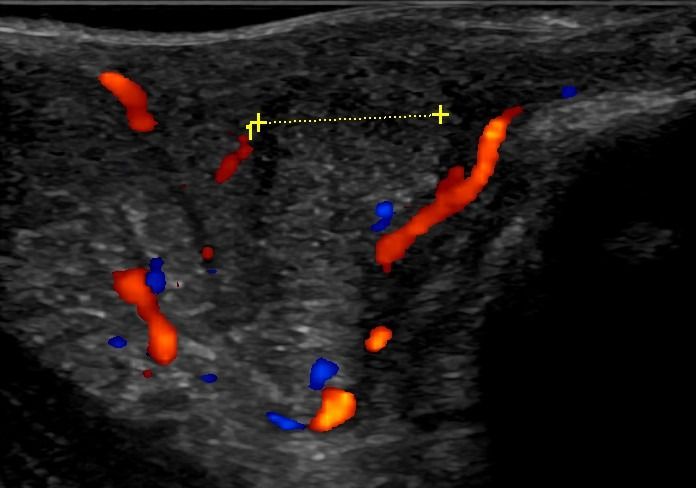

Πολλές αλλοιώσεις και παθήσεις μπορούν να απεικονιστούν υπερηχογραφικά και να μελετηθούν αξιόπιστα με τη βοήθεια του Έγχρωμου Doppler και της Ελαστογραφίας .

- Αιμαγγειώματα, αγγειοδυσπλασίες (αγγειακού τύπου βλάβες)